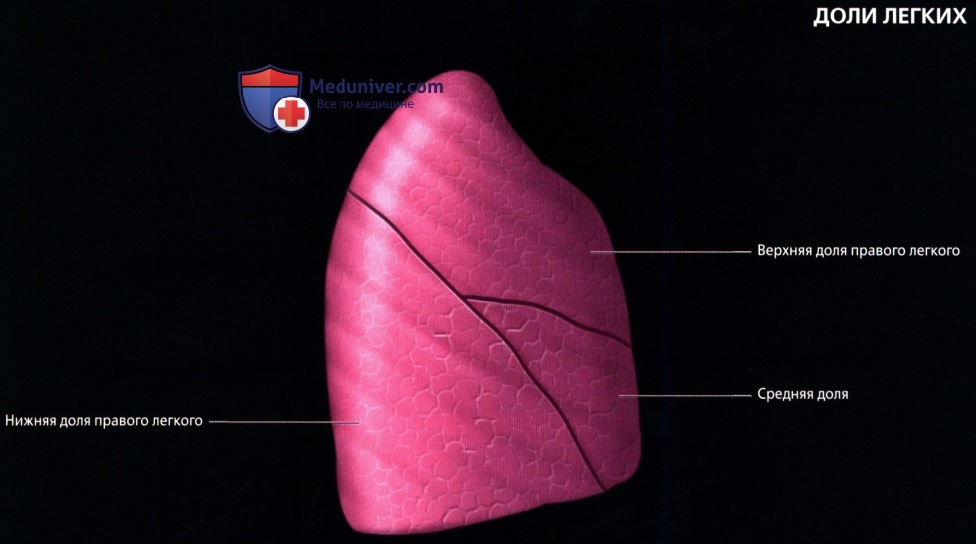

Анатомические изображения сегментов легких различных животных

Раздел: Другие животные